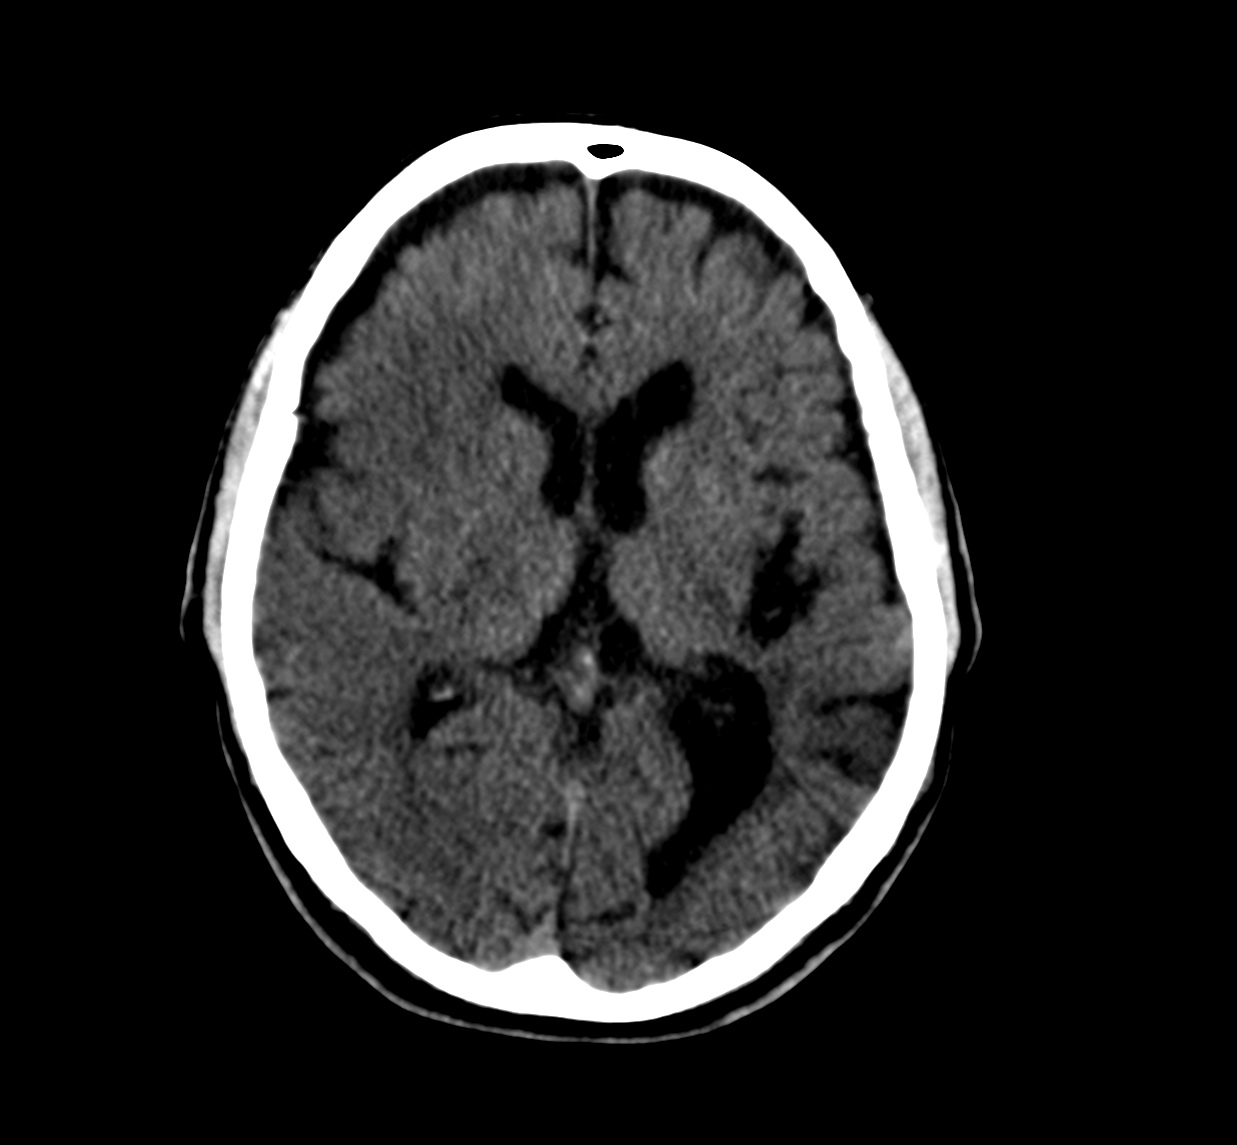

Se investiga un poco más y se descubre que el paciente había acudido diez días antes, también con cierta clínica de debilidad en hemicuerpo izquierdo, y se le realizó un TAC de cráneo. Observemos por tanto el estudio previo:

Pues bien, ante los hallazgos descritos, se clarifica que estamos ante un paciente el cual no tiene una masa y que ha sufrido una lesión isquémica hace diez días. Ahora, sobre dicha lesión, tenemos una imagen con un aumento de densidad que sugiere sangrado por una parte y otra hipodensidad en la perifería que correspondería a un edema. Por tanto, descartamos un sangrado intraparenquimatoso de novo. El paciente tiene más de 65 años, no es hipertenso, la imagen del sangrado no es de alta densidad, lo que se opone a una fase aguda o hiperaguda, y tenemos el TC de cráneo previo donde ya se advertía un proceso de tipo isquémico. Por tanto, nos quedan dos opciones, o estamos ante un resangrado de un ACV o estamos ante una Perfusión de lujo.